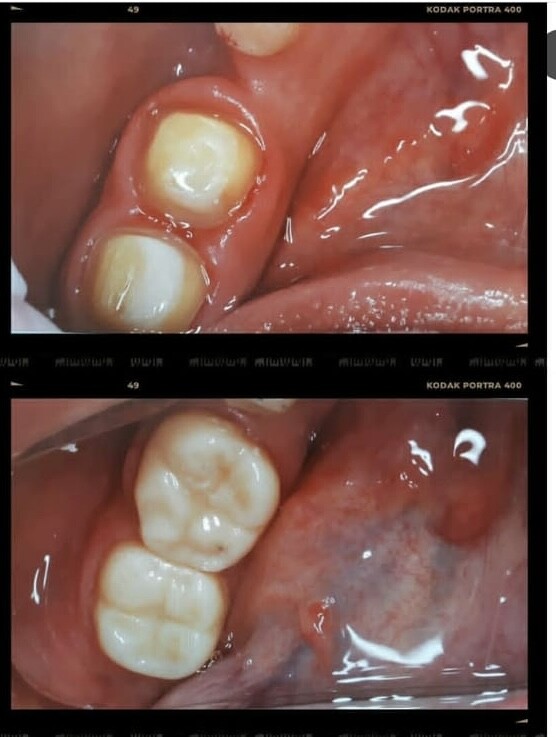

Лечение зубов

Лечение кариеса

Пломбирование зубов

Лечение пульпита

Реставрация зубов

Пломбы быстро выпадали или были неэстетичными, под пломбами возникал кариес, под коронками портились зубы, после лечения корневых каналов возникали кисты, после снятия брекетов зубы опять разъезжались.

КАК МОЖНО ВОССТАНОВИТЬ РАЗРУШЕННЫЙ ЗУБ, ЕСЛИ КОРЕНЬ СОХРАНИЛСЯ?

Если от зуба остался только лишь корень, это повод задуматься о целесообразности и возможности его сохранения. Решение всегда принимается совместно с пациентом, на основании клинической картины (степени разрушенности и состояния оставшихся тканей) и диагностических снимков, которые в полном объёме покажут состояние зуба и окружающих его тканей.

Чаще всего применяются различные штифтовые конструкции, которые на специальный цемент фиксируются в предварительно подготовленный корневой канал зуба. Таким образом восстанавливается культя будущего зуба, на которую в дальнейшем, после получения оттиска ортопед изготавливает коронку.